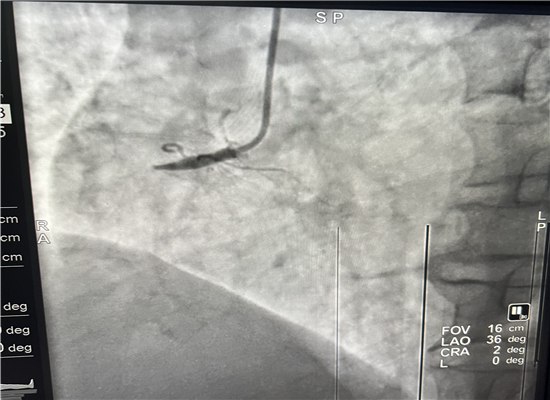

19时13分左右,一名患者因晚饭后行走不稳而请求出诊,急诊医学科医护人员火速赶往现场,到诊时测生命体征,输液后接回急诊医学科,回科后做心电图检查,诊断为急性心肌梗塞,随即通知心血管内科会诊,确定做急诊介入治疗,20时30分进入导管室,杨勇主任、张轩副主任共用21分钟就实现了心肌再灌注,挽救了患者生命。

介入手术前

介入手术后